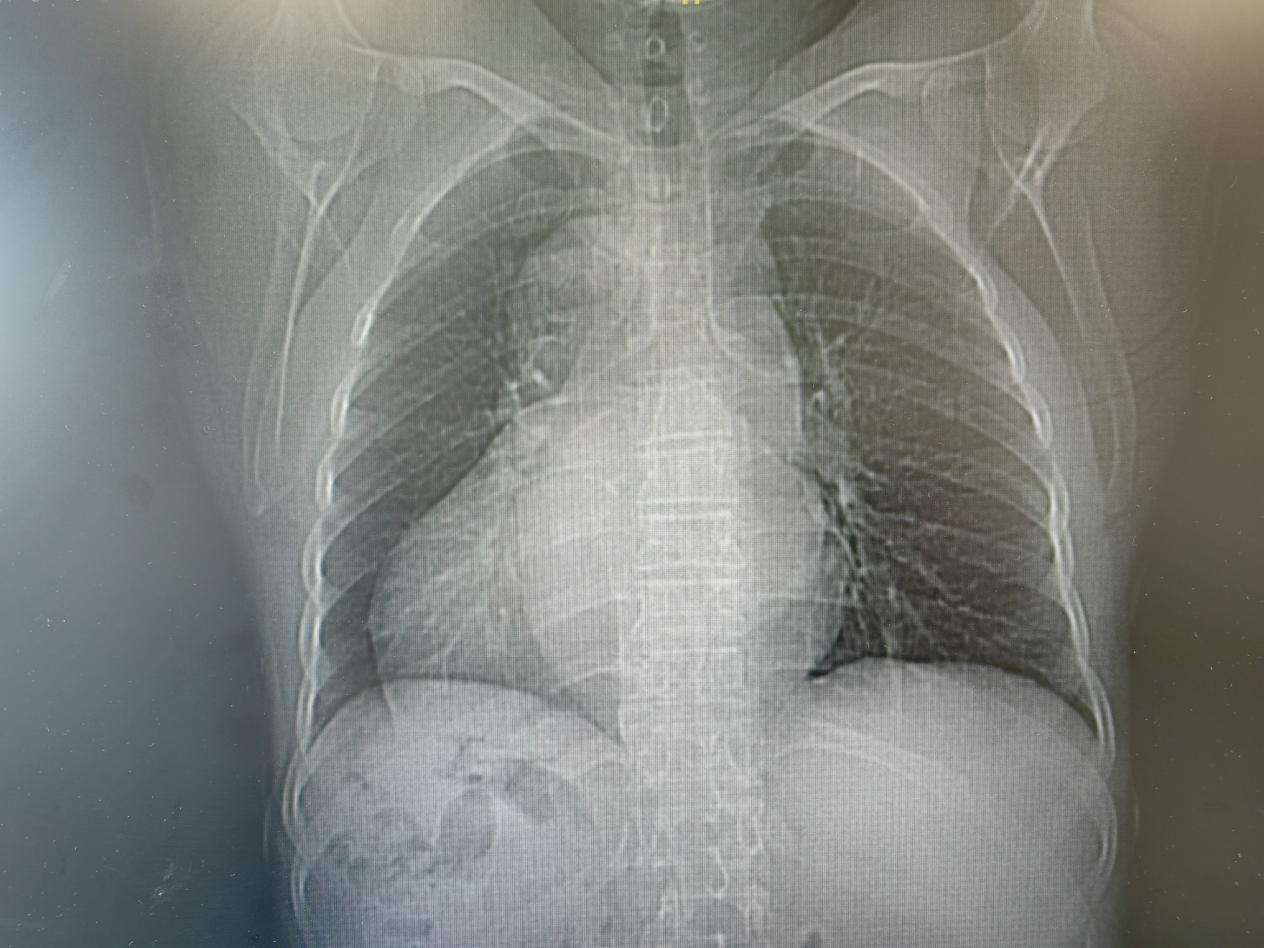

近一个月来,62岁的蔡女士时常觉得胸闷、心悸,特别是活动后喘得厉害,到华体会体育 检查后,被确诊为房颤。而更让人惊讶的是,与正常人心脏位置偏左,心尖部在胸腔左侧相反,蔡女士的心脏却罕见的长在了右胸,就像镜中倒影,一切都与常人相反。

患者的心脏罕见的长在了胸腔右侧